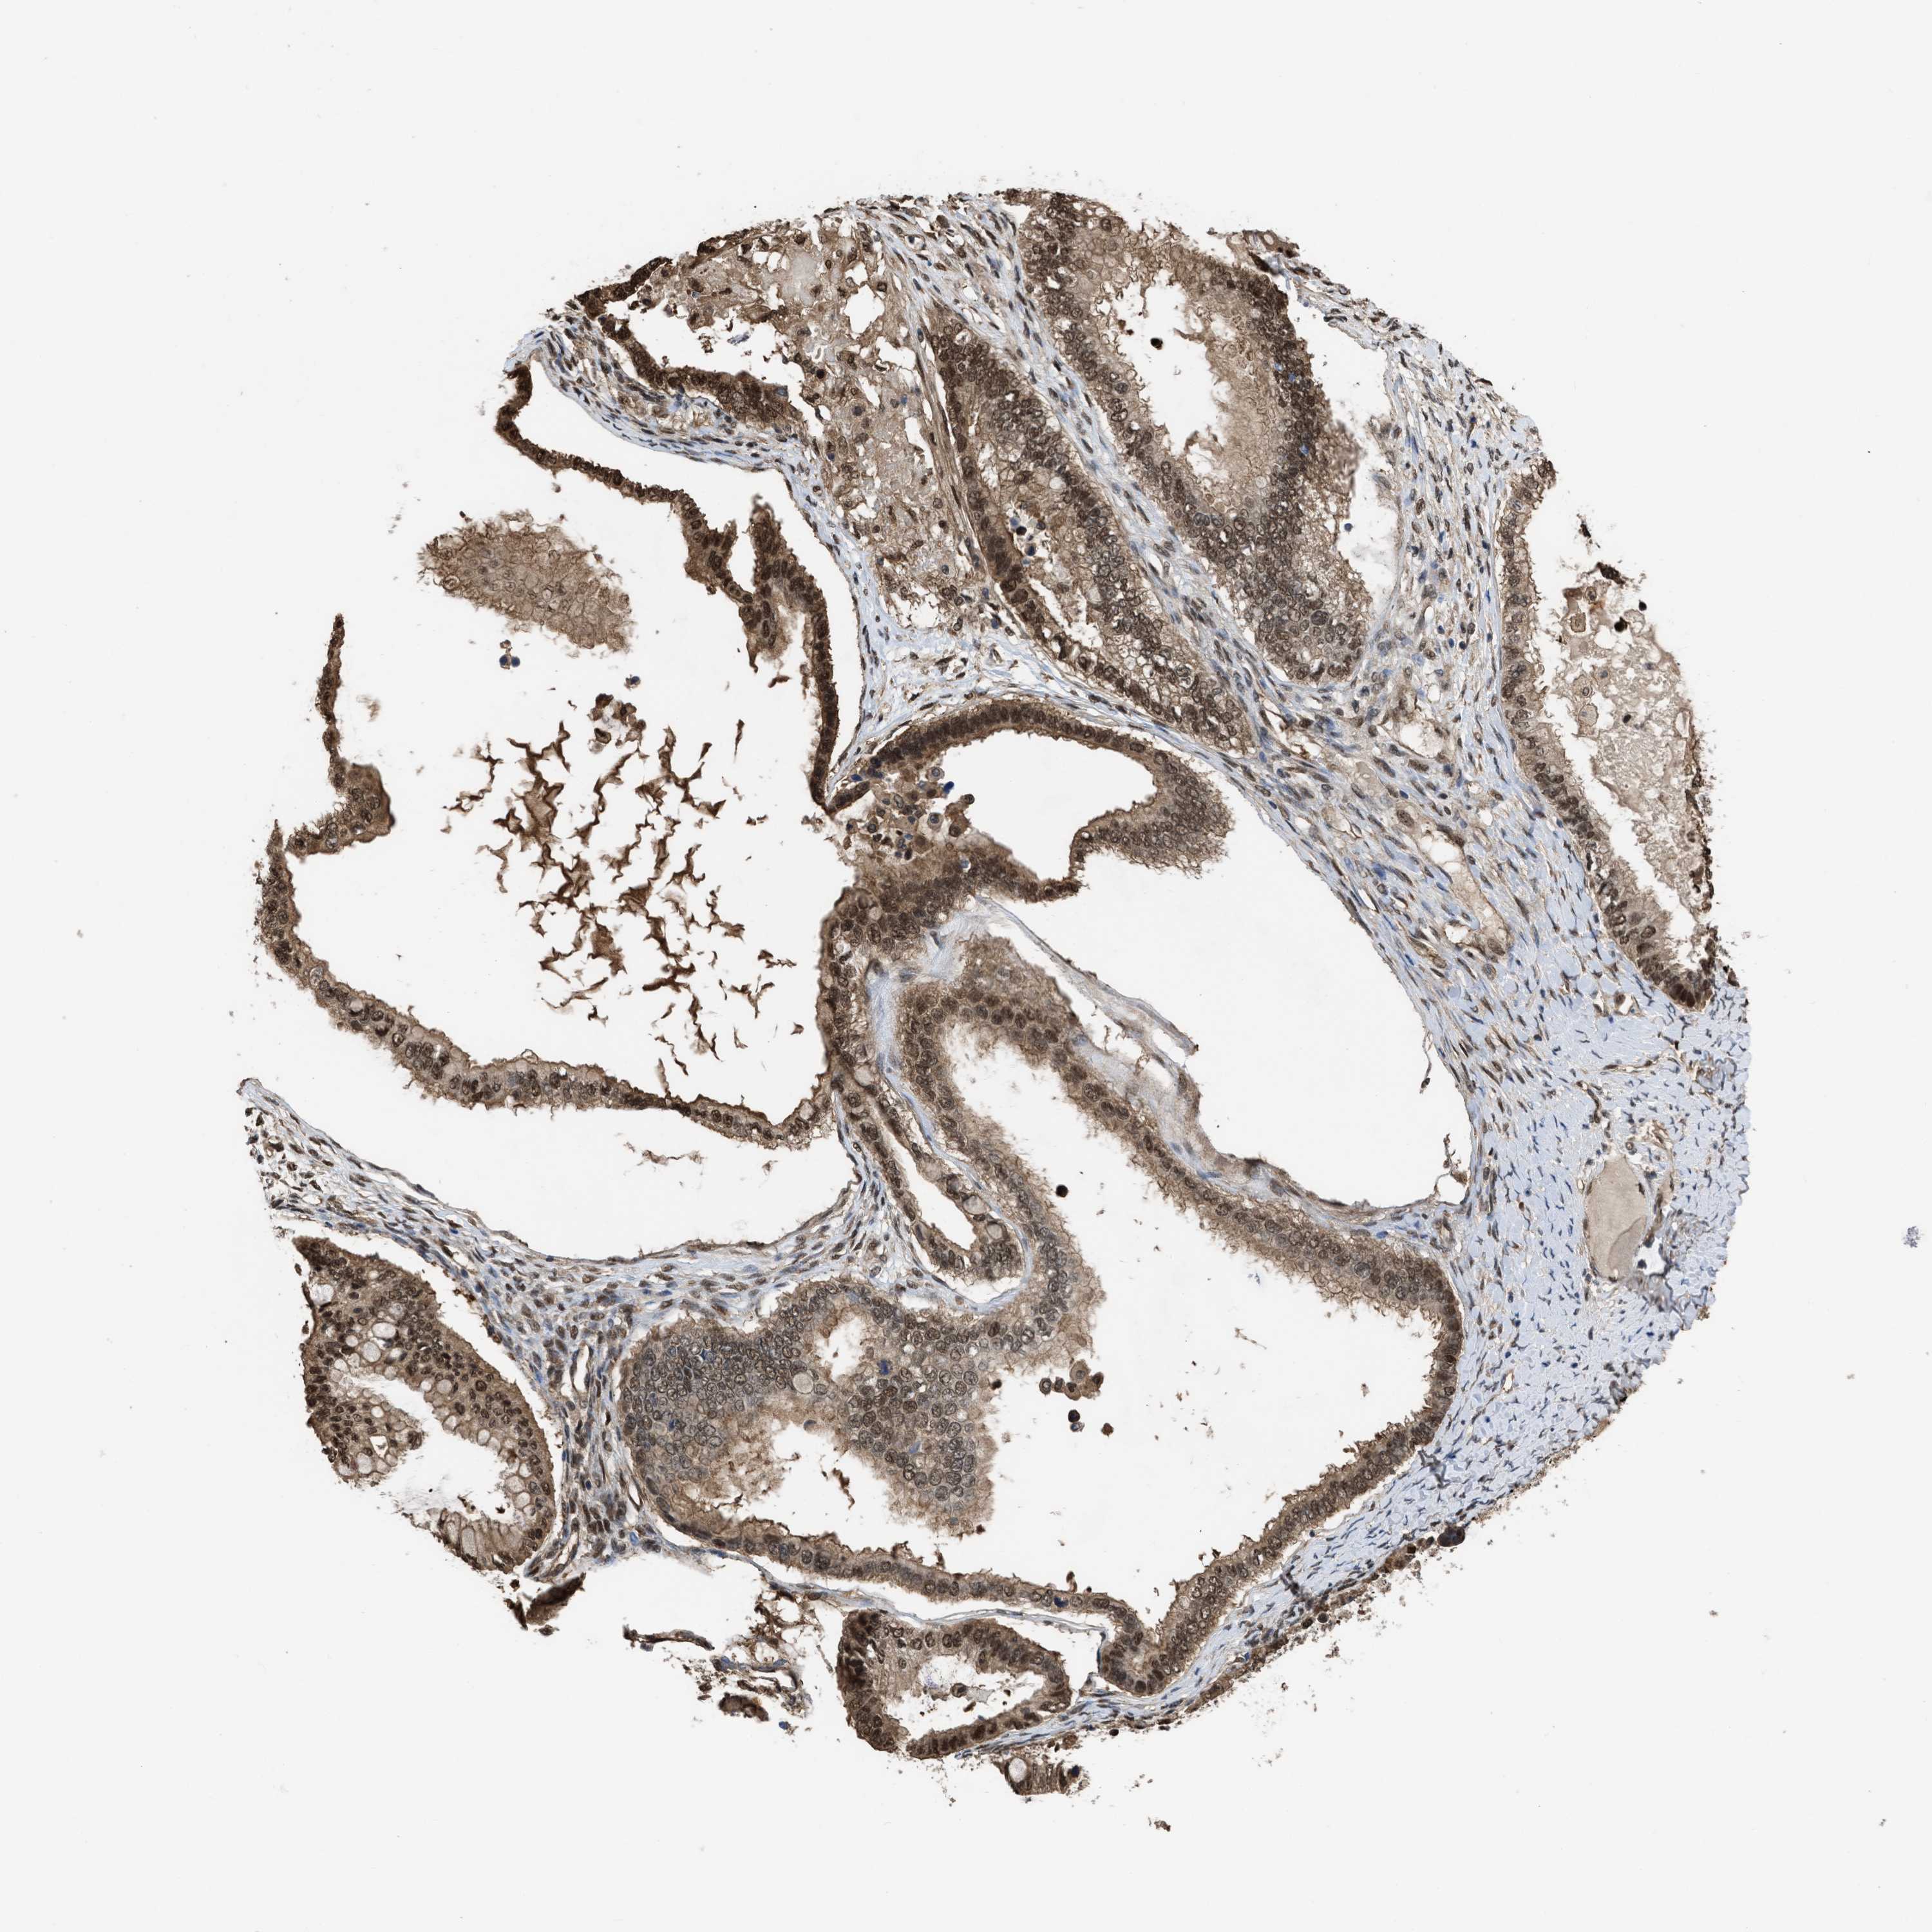

OVARIAN CANCER - Protein expressioni

A mouse-over function shows sample information and annotation data. Click on an image to view it in a full screen mode. Samples can be filtered based on level of antibody staining by selecting one or several of the following categories: high, medium, low and not detected. The assay and annotation is described here.

Note that samples used for immunohistochemistry by the Human Protein Atlas do not correspond to samples in the TCGA dataset.

Antibody stainingi

Antibody staining in the annotated cell types in the current human tissue is reported as not detected, low, medium, or high, based on conventional immunohistochemistry profiling in selected tissues. This score is based on the combination of the staining intensity and fraction of stained cells.

Each image is clickable and will lead to virtual microscopy that enables deeper exploration of all samples and also displays staining intensity scores, fraction scores and subcellular localization as well as patient and tissue information for each sample.

Antibody HPA026918

Antibody CAB013274

Antibody CAB018389

Staining

High

Medium

Low

Not detected

Cystadenocarcinoma, serous, NOS